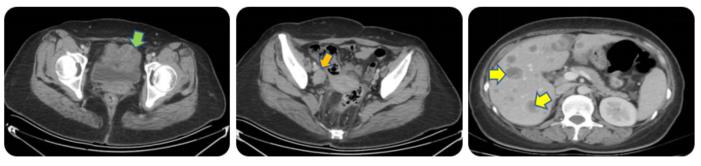

2023年1月28日CT提示,盆腔肿物5.5*8cm,右侧髂血管旁、骶前及肠系膜多发淋巴结,较前增大,肝单发转移进展为肝多发转移,大者3.6*2.4cm(图1)。

腹部CT提示:回盲部肠壁不均匀增厚,考虑恶性占位,伴周围系膜、肠系膜根部多发淋巴结恶性肿瘤(MT),肝内多发结节及肿块MT;左肺下叶前内基底段实性小结节;肝脏S2段,S8段,S5段,S6段四枚转移瘤,较大者约4.6*4.1cm(图2)。